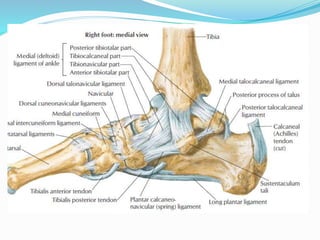

 MEDIAL COLLATERAL LIGAMENT /DELTOID

LIGAMENT:

apex at the tip of medial malleolus & base at talus,

navicular , calcaneum.

 Divided into 2 parts :

superficial & deep parts :

 Superficial deltoid : Resists the talar abduction &

resists the eversion of foot.

 Tibionavicular part of the ligament prevents

displacement of talar head inwards.

 Tibiocalcaneal portion prevents valgus displacement.

 Deep deltoid ligament :

It is an intraarticular part .

Prevents lateral displacement & external rotation of

talus.